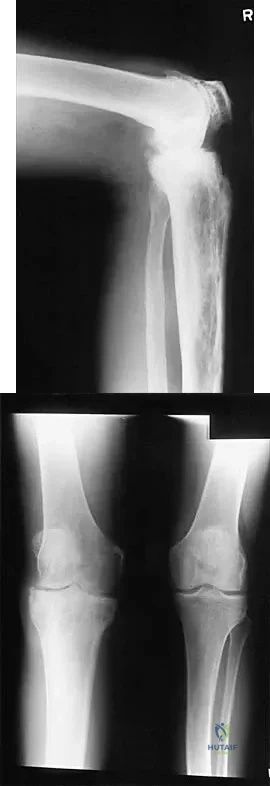

Question 37

Figures 14a and 14b show the initial radiographs of an 18-year-old man who fell while snowboarding. Figures 14c and 14d show the radiographs obtained following closed reduction. Examination reveals that the elbow is stable with range of motion. Management should now consist of